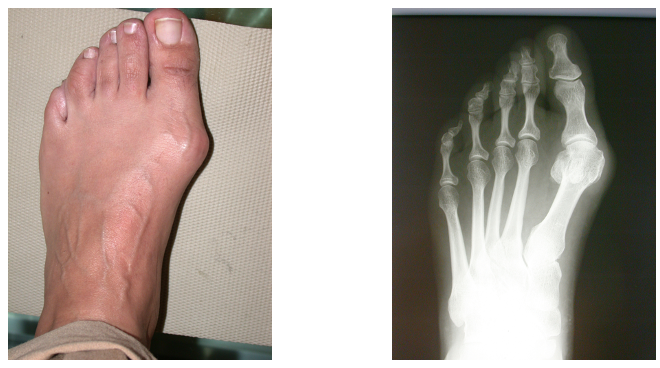

Klar ersichtlich der Druck des Schuhs auf die Grosszeh

Durch die Verschiebung des Knochens ziehen die Sehnen in eine falsche Richtung

Fuss praeoperativ